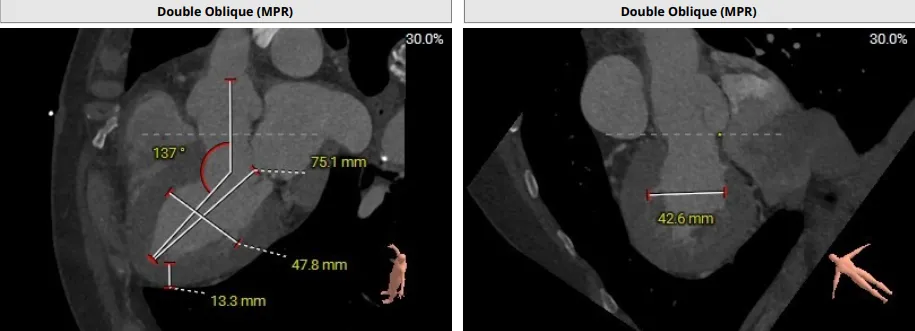

患者为主动脉瓣三叶瓣,瓣叶增厚,瓣叶未见明显钙化,存在三个瓣窦,窦部增大,分布较均匀;主动脉瓣环周长折算直径29.4mm;双侧冠脉开口高度可LCA:10.9mm,RCA:17.2mm;双侧冠脉未见明显钙化;最佳投射角度:右窦中心体位:CRA:16°/LAO:13°(其它参考角度如下图); 模拟切口位置:第6-7肋间;模拟输送器角度为143°;室间隔基底部稍增厚;升主动脉人工血管置换术后。